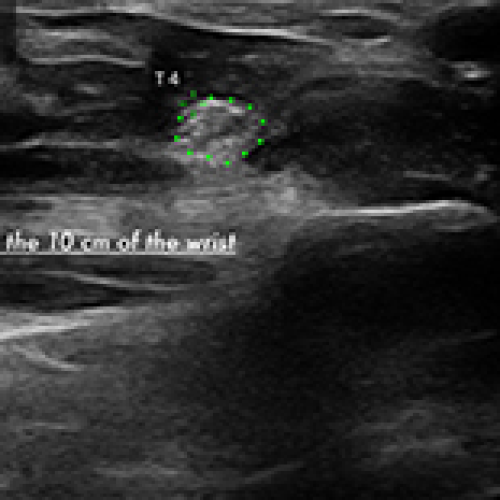

02 Nov 2024 : Clinical Research

Evaluation of Splint and Exercise Interventions for Carpal Tunnel Syndrome: Insights from Ultrasonographic Measurements

DOI: 10.12659/MSM.945704

Med Sci Monit 2024; 30:e945704

Sibel Çağlar

, Tuba Altun

, Meltem Vural

, Murat Mert

5,991